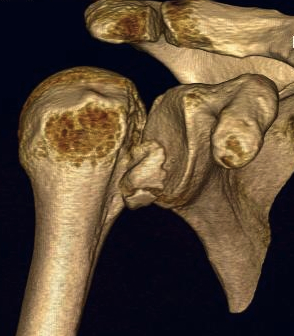

CT scan

Confirms dislocation

Reverse Hill Sachs

Humeral head defect

- caused by impaction of anterior humeral head on posterior glenoid

- intra-articular

- measured as a percentage of the articular surface

Lesser tuberosity fractures

Posterior glenoid fractures / bony bankart